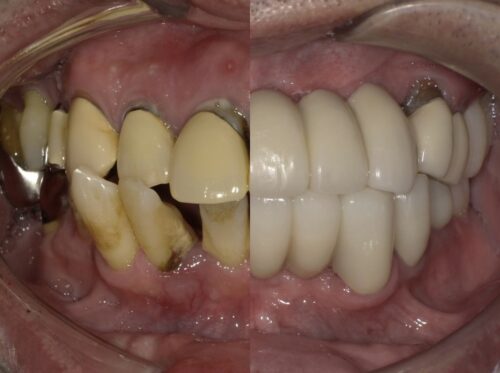

審美治療 症例集 虫歯治療

銀歯を白くしたい…セラミックインレーで自然にきれいにできるって知っていますか?

「できるだけ白いものに変えたい」そんなご相談から始まった症例です

「銀歯が目立つからきれいにしたい…… 歯科コラム